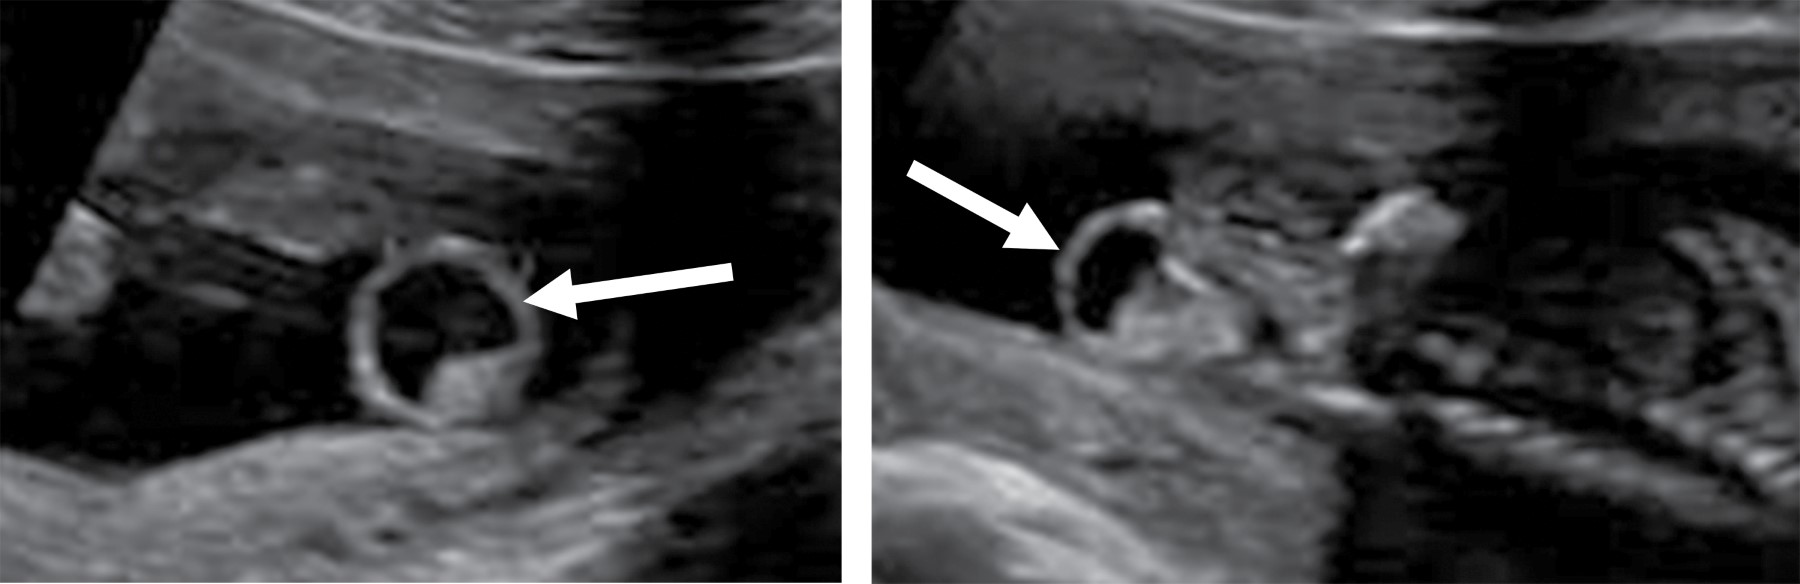

El abordaje diagnóstico imagenológico es esencial para demostrar la extensión intraabdominal y los efectos en las estructuras adyacentes. Los hallazgos por imagen del teratoma van acordes a sus componentes. Por radiografía se observará una masa de dimensiones variables que puede estar asociada a calcificaciones.10 El ultrasonido mostrará una masa de ecotextura heterogénea con presencia de focos ecogénicos de calcificaciones y grasa así como áreas quísticas anecoicas. El modo Doppler color demuestra que los componentes sólidos presentan vascularidad de moderada a alta.10,11 La tomografía computarizada muestra una masa con densidad heterogénea por sus componentes de grasa, calcio, tejidos blandos y niveles de líquido. El medio de contraste muestra un patrón de reforzamiento variable en los componentes sólidos. La resonancia magnética presenta hallazgos con intensidad de señal heterogénea. En T1 la grasa se aprecia hiperintensa, los tejidos blandos isointensos, el componente quístico hipointenso y el calcio marcadamente hiperintenso. En T2 se observa el componente quístico hiperintenso y el calcio marcadamente hipointenso. El T1 con contraste presenta un reforzamiento heterogéneo del componente sólido.3,10 Los hallazgos por imagen no pueden predecir subtipos histológicos de tumores, pero existen características de benignidad y malignidad. El componente quístico, las calcificaciones y el contenido graso prominente corresponden a hallazgos más comúnmente observados en lesiones benignas. La hemorragia y/o necrosis dentro de la masa, mayor componente sólido y realce heterogéneo con contraste son más sugestivos de malignidad.3,6 El diagnóstico prenatal se realiza con ultrasonido obstétrico y/o con resonancia magnética fetal, identificando una masa sacra heterogénea con componentes quísticos y sólidos.2,3 Postnatalmente la resonancia magnética permite la diferenciación de tejidos, extensión intramedular y pélvica, siendo superior a la tomografía computarizada al no exponer a una dosis de radiación ionizante.12 Se debe realizar diagnóstico diferencial principalmente con mielomeningocele, lipomas, hemangiomas, quiste pilonidal y epidermoide.2,7 El neonato puede presentar complicaciones cardiacas, anemia e hidrops fetal. Durante el parto puede ocurrir ruptura del teratoma y hemorragia al ser altamente vascular. Si es suficientemente grande puede ocasionar efecto de masa en estructuras adyacentes.2,3,13 El tratamiento es principalmente quirúrgico, ya sea prenatal o postnatal. La cirugía fetal intrauterina es una opción en fetos de alto riesgo como los productos con hidrops fetal. Postnatalmente la resección quirúrgica temprana se realiza para evitar progresión a malignidad y recurrencias. Los pacientes con teratoma maligno requieren manejo combinado de cirugía, quimioterapia y radiación.3,14

Paciente femenino de 32 años de edad sin antecedentes de importancia. Tomó ácido fólico previo al embarazo. Gesta dos, cesárea uno. Su primera consulta del embarazo actual fue a las 7.2 semanas de gestación (SDG) con longitud cráneo caudal acorde a la edad gestacional estimada por fecha de última menstruación. En la semana 12 se realizó ultrasonido estructural donde se observó aparente defecto a nivel sacro que parecía tener continuidad con médula espinal. En el ultrasonido a la semana 16 se apreció una imagen de contenido anecoico en la región sacra y con aparente continuidad al canal medular, en probable relación con mielomeningocele (Figura 1). En la semana 20 se realizó amniocentesis y posteriormente microarreglos encontrando complemento cromosómico 46 XX, sin alteraciones en las regiones analizadas. Se realizó tamiz de glucosa y curva de tolerancia a la glucosa en la semana 27 diagnosticando diabetes gestacional, sólo requirió manejo dietético. En la semana 26 se realizó ultrasonido identificando en región glútea una imagen con ecotextura heterogénea de predominio anecoico, con medidas aproximadas de 3.3 × 3.2 cm, que no comprometía genitales y parecía corresponder a un teratoma sacro. Se realizan seguimientos ultrasonográficos con Doppler fetal y pruebas de bienestar fetal hasta el término. A las 38.2 SDG nace por cesárea producto femenino con peso de 2,669 g y talla de 48 cm. Llora y respira al nacer, se dan maniobras básicas de reanimación. Se califica con APGAR 9/9 y Silverman Anderson de 0. Ingresa a terapia intermedia. En la exploración física neurológicamente no mostró alteraciones, la fuerza y sensibilidad de las extremidades estaba conservada, sin movimientos anormales. En la región sacra se identificó una masa con tamaño aproximado de 2 × 2.5 cm que presentó sangrado en capa, la cual de forma atípica no tenía una cobertura de piel (Figura 2). Se realizó radiografía de pelvis, ultrasonido abdominal, transfontanelar y de región sacra. Se tomó radiografía anteroposterior y lateral de pelvis que reveló integridad de los cuerpos sacros y los elementos del arco posterior sin alteraciones aparentes así como una masa con densidad de tejidos blandos inferior a la región del sacro (Figura 3). En el ultrasonido abdominal no se reportaron alteraciones, se valoró la vejiga y riñones, mismos que mostraron situación, morfología y ecogenicidad normales. El ultrasonido transfontanelar no mostró anomalías. Se realizó rastreo con transductor lineal multifrecuencia en escala de grises y con modo Doppler color de la columna lumbosacra (Figura 4). Se decidió realizar resonancia magnética para mejor caracterización de la extensión de la masa descrita. Se efectuaron secuencias multiplanares de la columna lumbosacra y panorámica sagital de la columna completa (Figura 5). Se realiza la resección completa de la tumoración, respetando estructuras pélvicas y lográndose una cobertura completa sin tensión de la herida. Adecuada recuperación postoperatoria, por dehiscencia parcial de herida se maneja sistema VAC ambulatorio, el cual es una terapia no invasiva que utiliza presión negativa sobre la herida para ayudar a la cicatrización en un medio húmedo y cerrado, lo que favorece la angiogénesis, el tejido de granulación y disminuye la colonización bacteriana (Figura 6). Niveles séricos de alfa fetoproteína y fracción beta de gonadotropina coriónica preoperatorios normales. El reporte de patología reveló teratoma inmaduro (elementos inmaduros menores de 1%), superficie externa con piel ulcerada. Después de un año de vigilancia, no hay datos de recidiva clínica o por laboratorio.

Es importante hacer el diagnóstico diferencial con el mielomeningocele, lipomas, hemangiomas, quiste pilonidal y epidermoide.3 Éstos tienen una localización posterior al sacro. El teratoma sacrococcígeo tiene una localización entre el coxis y el ano y tiende a estar recubierto por piel.2 Asimismo, se debe evaluar la médula espinal, dado que el mielomeningocele tiene afectación asociada de la misma.11 En este caso se constató la integridad de los cuerpos sacros y del arco posterior así como del canal medular mediante la valoración con radiografías, ultrasonido y resonancia magnética.